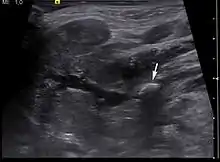

Diagnosis is usually made by characteristic history and physical examination. Diagnosis can be confirmed by x-ray (80% of salivary gland calculi are visible on x-ray), by sialogram, or by ultrasound.

- "UOTW #70 - Ultrasound of the Week". Ultrasound of the Week. 24 April 2016. Retrieved 27 May 2017.